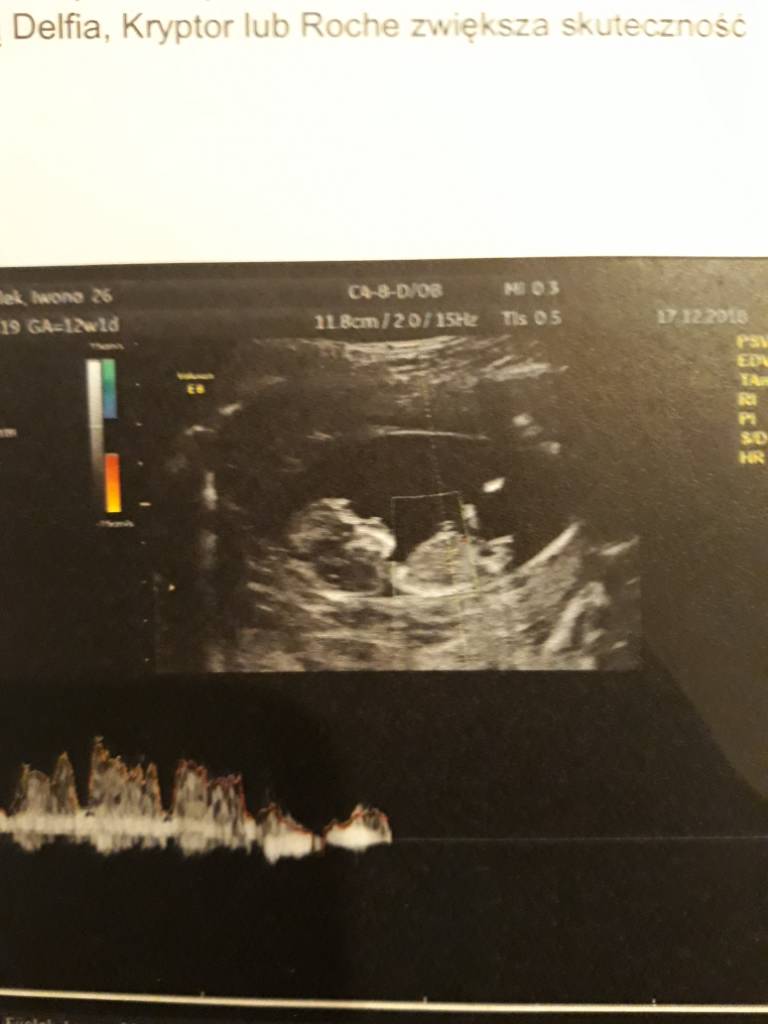

A no i dolaczam zdjecia moich Kabanoskow - jeden leniuszek ladnie pozowal a drugi wyglada jak kosmita bo sie ruszal , dzis tez do mnie machal !

A no i dolaczam zdjecia moich Kabanoskow - jeden leniuszek ladnie pozowal a drugi wyglada jak kosmita bo sie ruszal , dzis tez do mnie machal !ale z dzis zdjec nie mam bo to byl szybki.poglad ze wzgledu na upadek... aaa plecy bola ;(